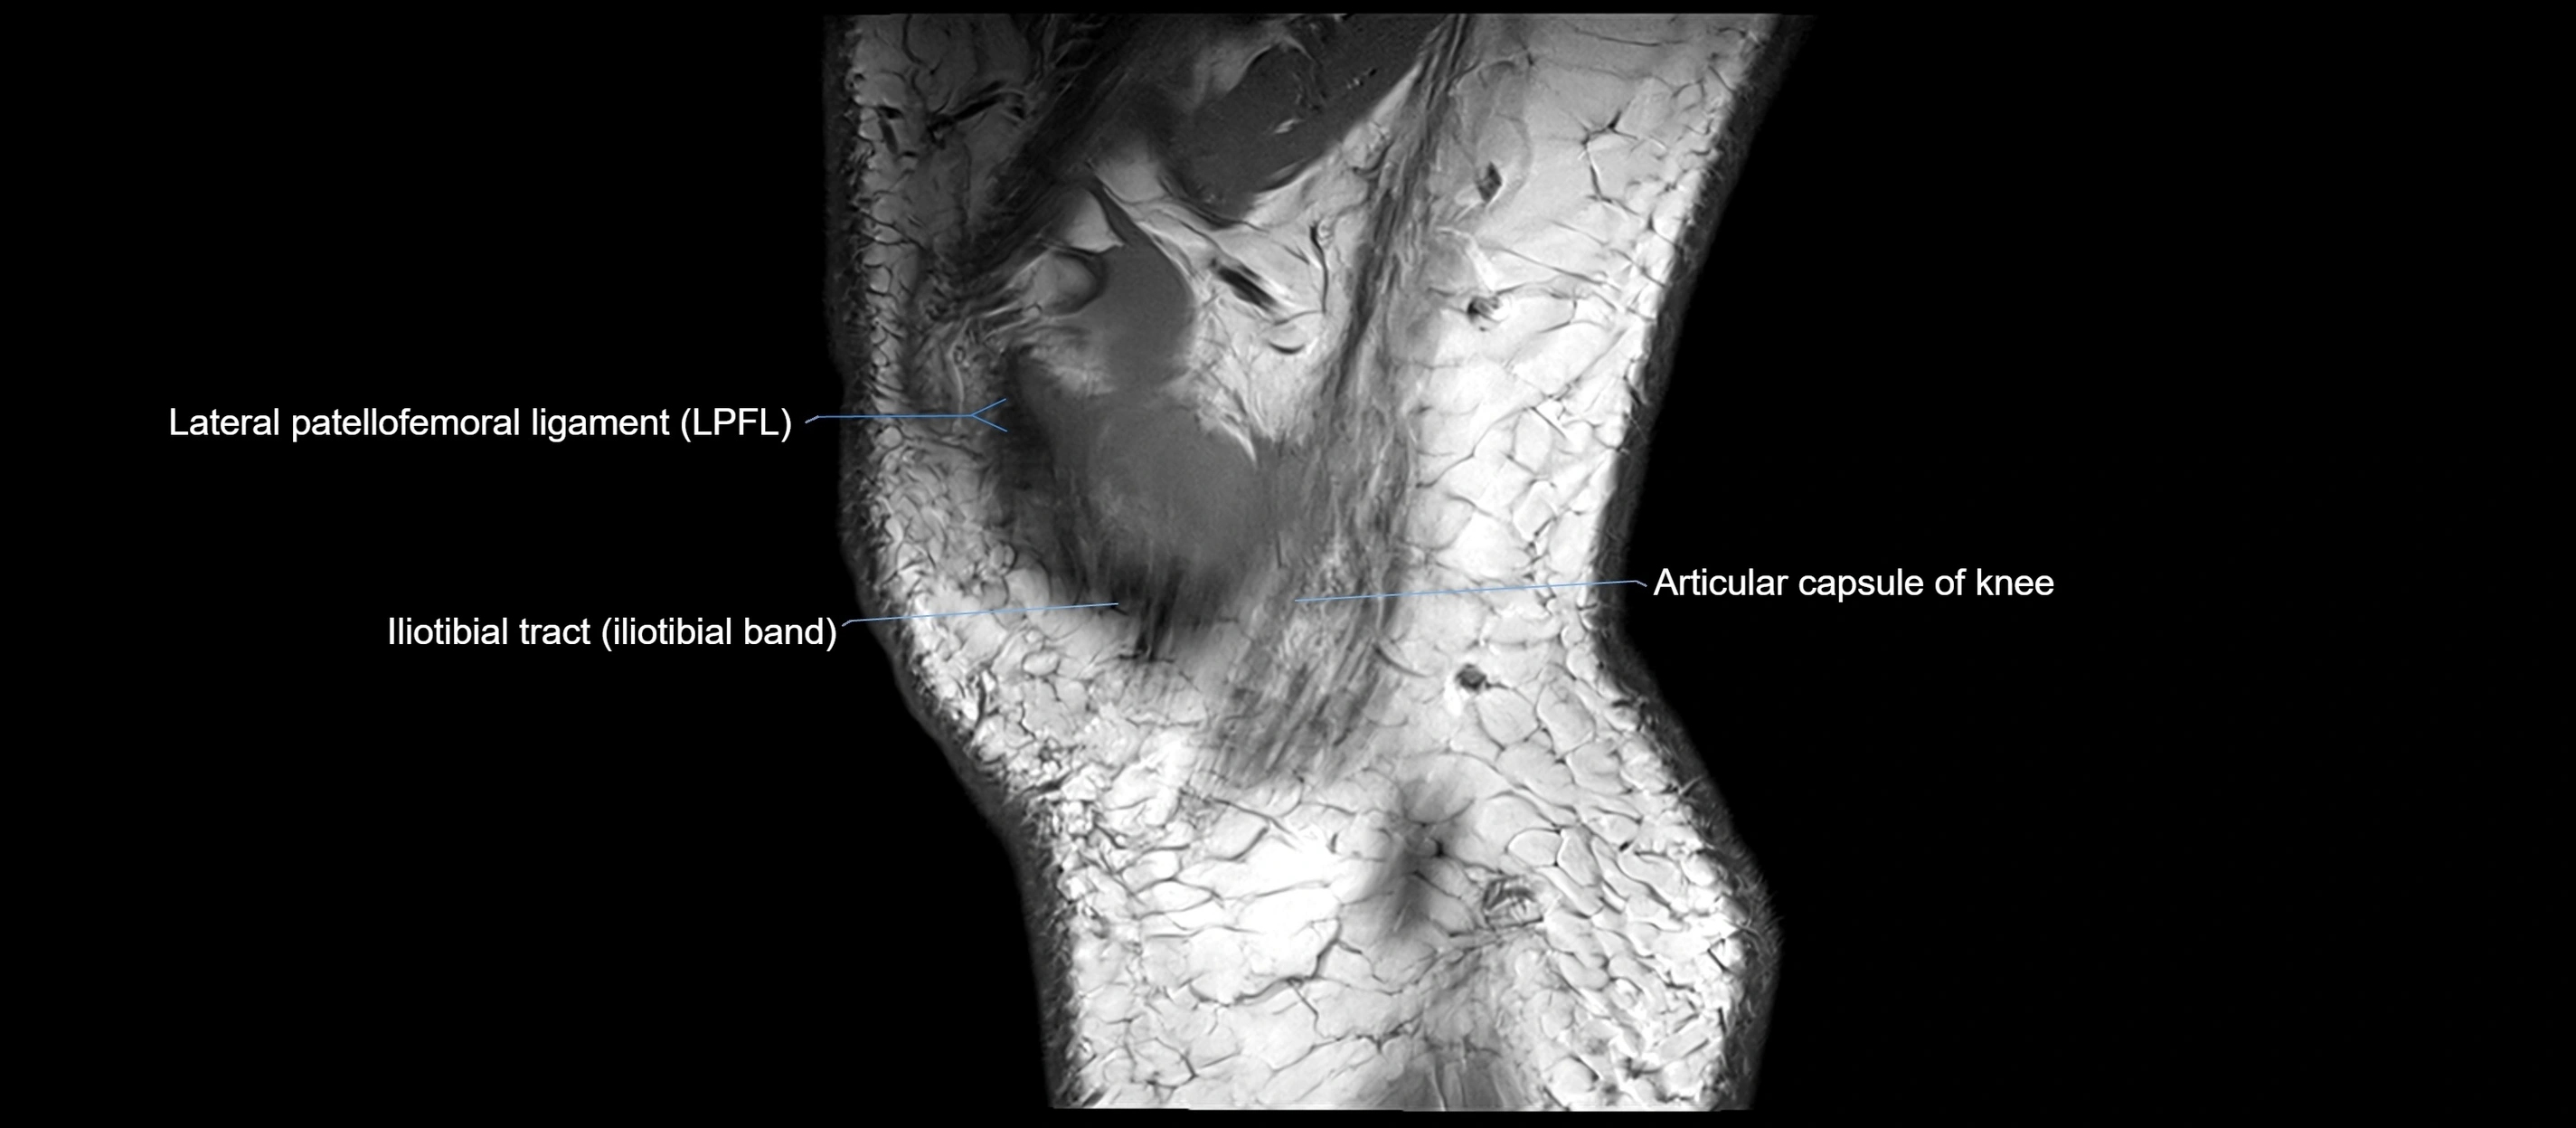

MRI images

image